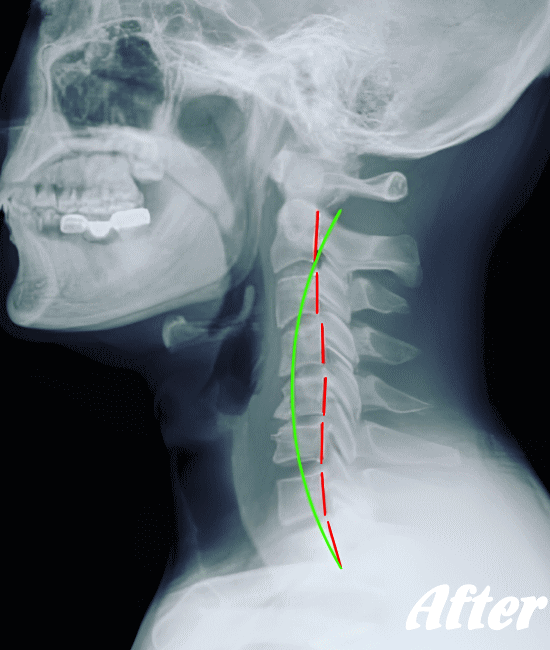

ストレートネックも、首に負担がかかりやすいので、注意が必要です。

HALOカイロプラクティック☆平和島整体院では、首の筋肉をゆるめていくため、まずは骨盤(特に仙腸関節)を調整、背骨(腰椎、胸椎、頚椎)を調整、そして肩甲胸郭を調整します。

そして、肩甲胸郭、つまり肩甲骨の動きをよくし、肋骨を広げ、丸まった背をのばし、胸が大きく広がるように調整します。肩甲骨には首の筋肉がつながっているので、調整は必須です。

状態に応じて、頭蓋骨を調整し、身体をリラックスさせます。基本的に、頚性神経筋症候群は姿勢の悪さに起因するところが大きいので、深く呼吸できる身体に改善していくことで、首のコリは取れていきます。